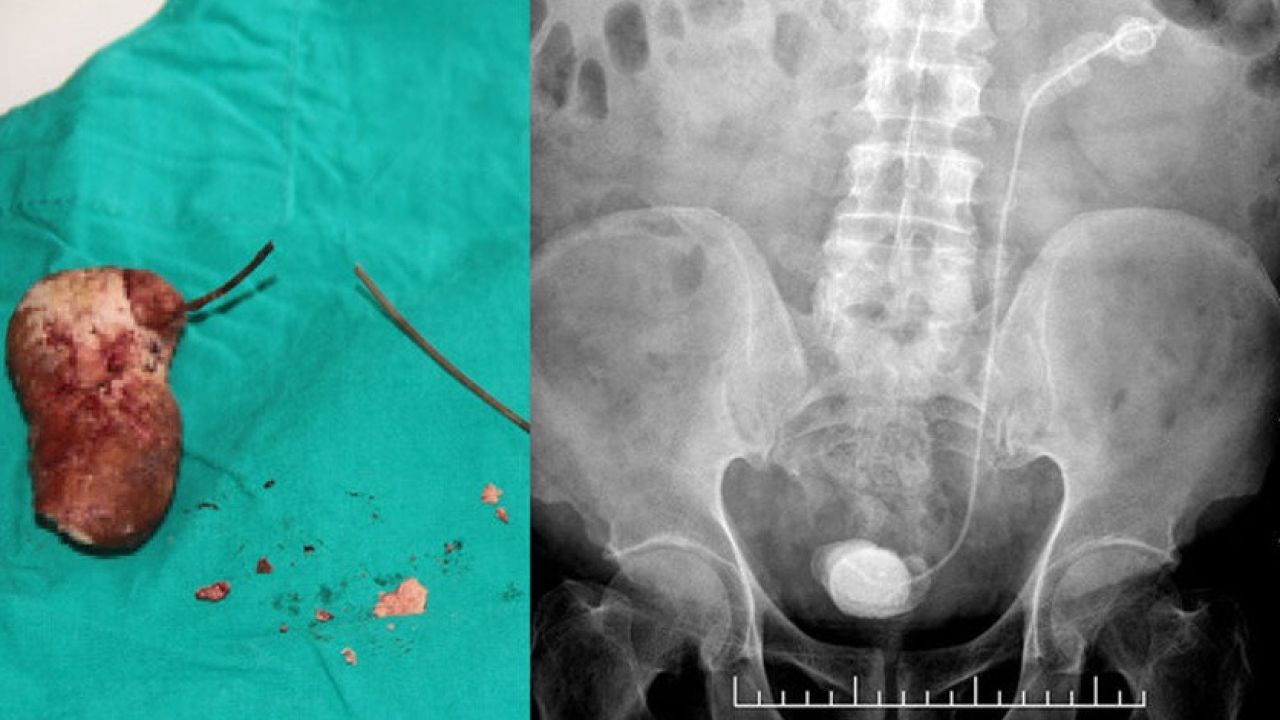

Elazığ’da yaşayan 3 çocuk babası Kadir Elban (69), idrar tutamama ve yanma şikayeti ile Fethi Sekin Şehir Hastanesine başvurdu. Burada Üroloji Uzmanı Op. Dr. Kadir Yıldırım tarafından tetkikler sonucu Elban’ın böbrek kanalında 28 santimetre stent olduğu, stendin etrafında ve mesanede taş oluştuğu fark edildi.

Dr. Yıldırım'ın hastaya sorması üzerine Elban’ın 7 sene önce Ankara’da bir hastanede bağırsaklarından ameliyat olduğu ve stent takıldığı öğrenildi. Bunun üzerine Op. Dr. Yıldırım tarafından yapılan operasyonla unutulan stent ve etrafındaki taşlar alındı.

Hastanın 7 yıl önce bağırsak operasyonu geçirdiğini belirten Op. Dr. Kadir Yıldırım, “Bu işlem sırasında DJS stent uygulanıyor ve 1 ay içerisinde alınması gerekiyor. Bu stent bazen hekim veya hasta kaynaklı unutulabiliyor. Bu hastamızda da böyle bir talihsizlik olmuş.

7 yıl boyunca böbrekte ve kanalında kalmış. Bu süre zarfında böbreklerde ileri boyutta taşlaşma olabiliyor. Bu tür durumlarla dünyada ve ülkemizde karşılaşılabiliyor. Bu hastanın tedavisinde endoskopik ameliyatlar dizisi ile tek seansta taşsızlık sağladık ve stendi çıkardık.

İlk başta böbrek kanalındaki taşlar lazer ve pnömotik litotriptör (havalı sistem ile taş kırma işlemi) ile kırıldı. Takiben böbrek üst polündeki 7 santimlik taş, fleksibl renoskop ile kırıldı” dedi.

Mesanede de 8 santimlik bir taşın oluştuğuna değinen Op. Dr. Yıldırım, “Bunu küçük bir kesi ile çıkardık. Hastamızın genel durumu iyi ve takiplerimize devam ediyoruz. 7 yıl çok ciddi bir süre. Aslında 1 yıl bile geç denilecek bir zaman ama 7 yıl kalmış. Hasta hem şanssız hem de şanslı. Böbreği tamamen kaybetmiş olabilirdik. Bazen bu durum ciddi enfeksiyon ataklarına yol açabilir. Böbreğin alınmasına kadar gider durumlara yol açabiliyor.

Böbrek fonksiyonlarına bir miktar etkilenme olsa da stendi çıkardığımız takdirde devam edebilecek düzeyde sağlıklı böbrek parenkimi vardı. Bu şekilde stendin çıkartılması hastanın tedavisi için yeterli” diye bilgi verdi.